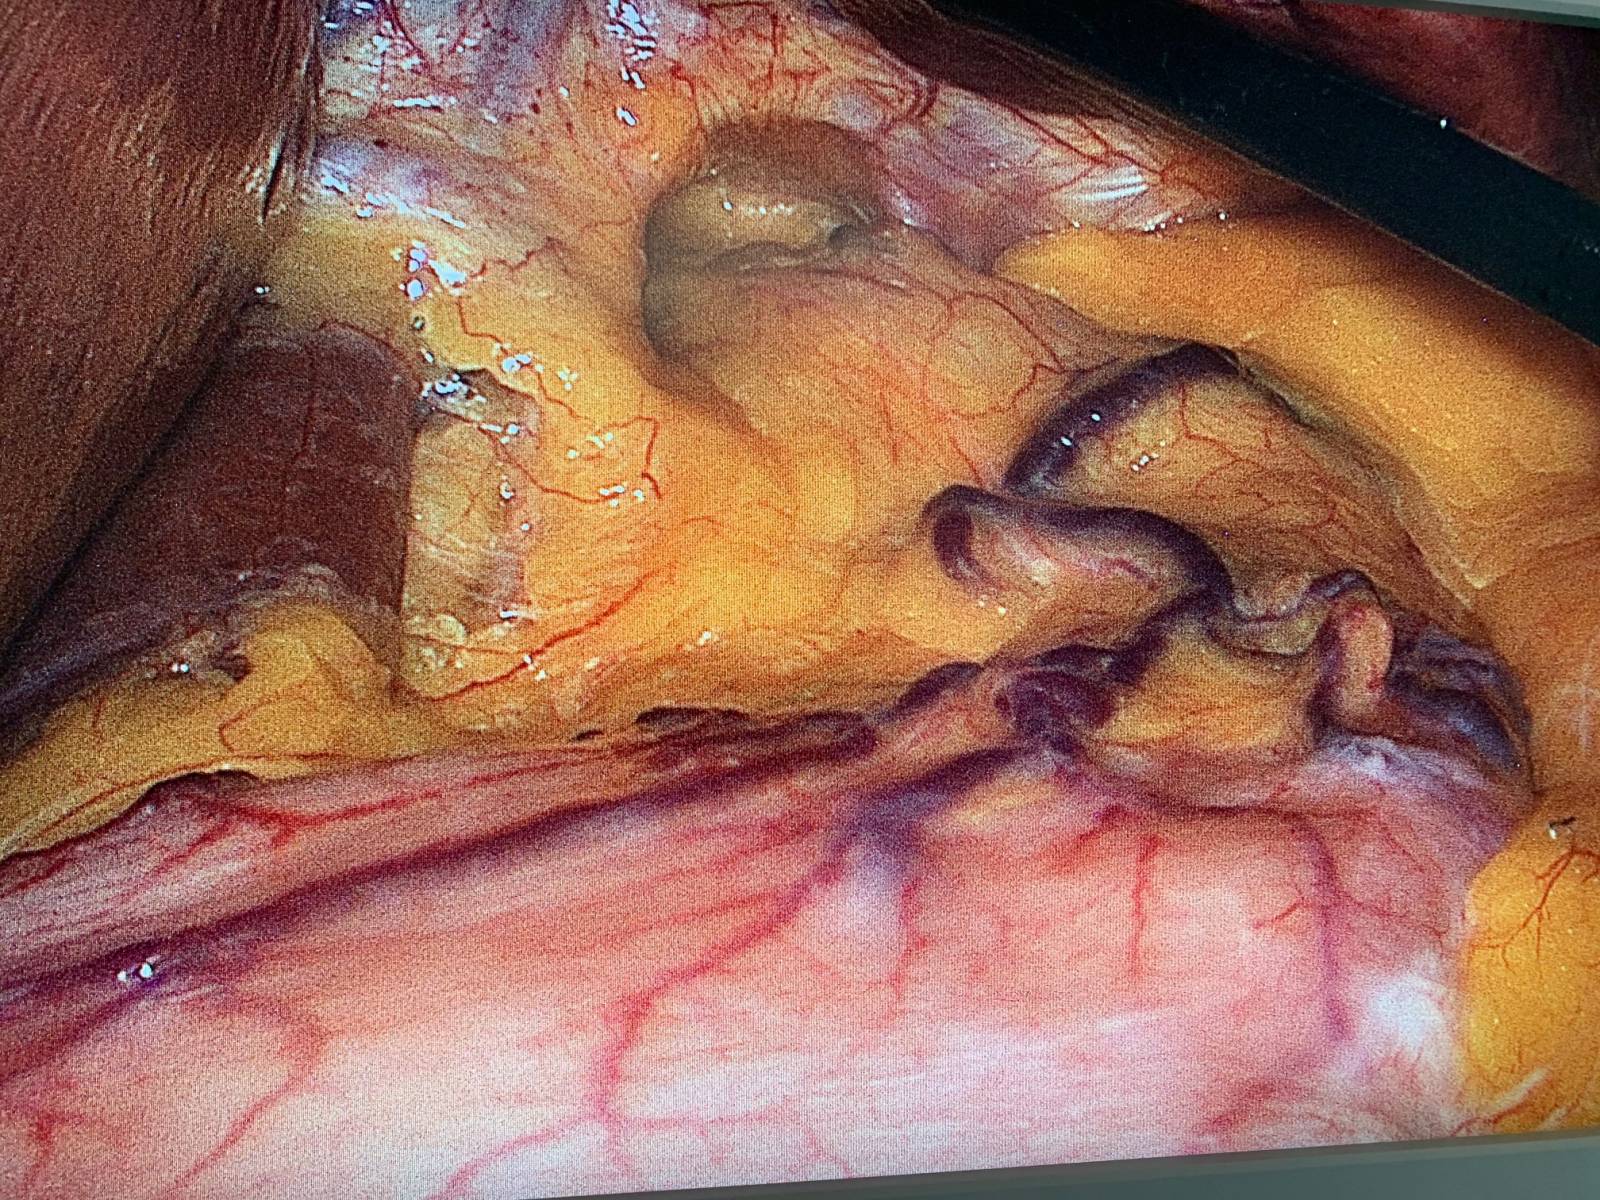

1.	Traitement chirurgical des complications fonctionnelles après sleeve : la conversion en bypass gastrique en Y.

Au cours de cette dernière décennie, la gastrectomie longitudinale laparoscopique  (LSG) ou Sleeve est devenue la procédure bariatrique la plus réalisée en Fr...

Sleeve gastrcetomie par les chirurgiens du groupe MUST

La Sleeve Gastrectomie, "comment je fais": réponse du Groupe MUST à Paris.

La sleeve gastrectomie est une spécialité des chirurgiens digestifs du groupe MUST à Paris. Le Dr Antoine Soprani, Fondateur du Groupe MUST à Paris nous exp...